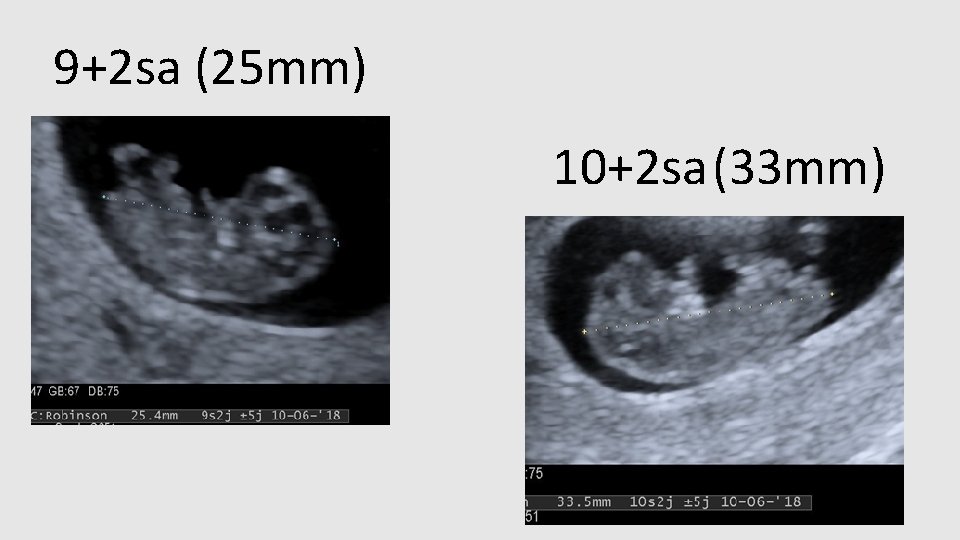

9+2 sa (25 mm) 10+2 sa (33 mm)